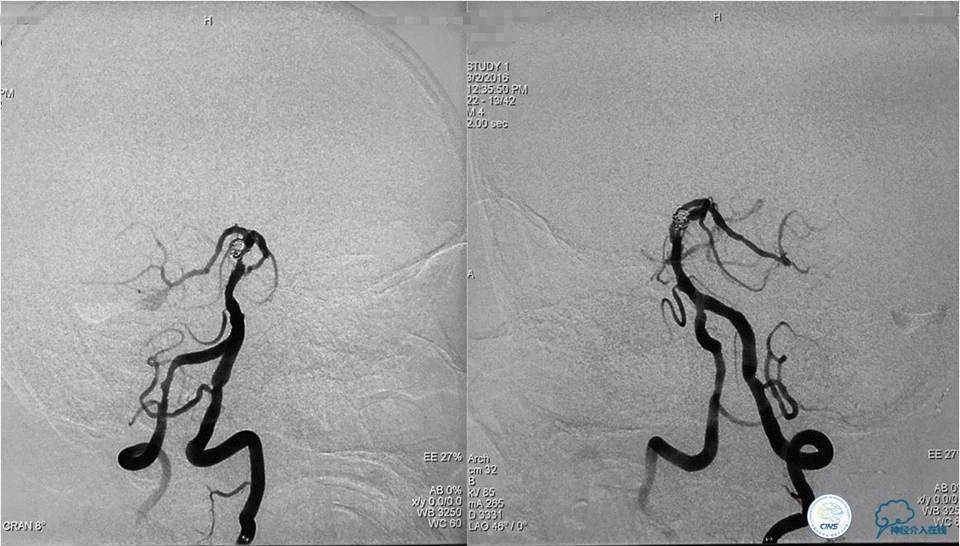

(2)支架结合弹簧圈栓塞动脉瘤

将Traxcess14引导Headway17准备送入下干,微导丝能够顺利进入下干,但微导管无法跟进,被LVIS JR支架网丝卡住,此时发现支架变形,呈灯笼状完全覆盖下干。

工作位造影

Traxess14微导丝携带Echelon10直头微导管穿过LVIS JR支架网孔进入瘤腔内,送入弹簧圈数枚并解脱,直至造影显示动脉瘤完全栓塞,解脱左后1枚弹簧圈。行工作位及标准正侧位造影。